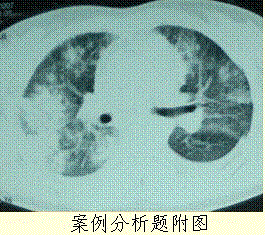

问题 患者女,23岁。间断发热伴皮疹1年半,诊断红斑狼疮。长期间断应用糖皮质激素治疗。近20 d高热(T 39℃)伴咳嗽咳痰, CT(附图)示双肺满布圆形密度增高阴影,大小不等,密度不均匀,上、中肺野分布较多,双侧少量胸腔积液。血常规:WBC 2.52×10/L, N 0.62, Hb 92 g/L;ESR 40 mm/h;痰真菌培养:烟曲霉3次阳性;支气管镜检查右下叶、左舌段见黄色黏液性血性分泌物,毛刷找到霉菌孢子。 本病例诊断属于

选项 A.确诊(Proven) B.临床诊断(Probable) C.拟诊(Possible) D.定植(Colonization) E.影像诊断

答案 B